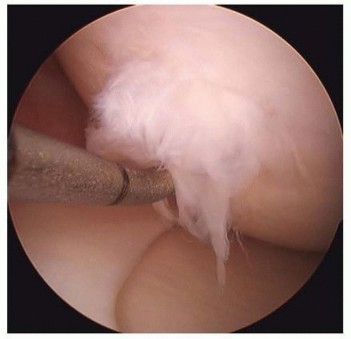

Osteochondritis Dissecans and Large Osteochondral Defects of the Knee DEFINITION Osteochondritis dissecans (O…